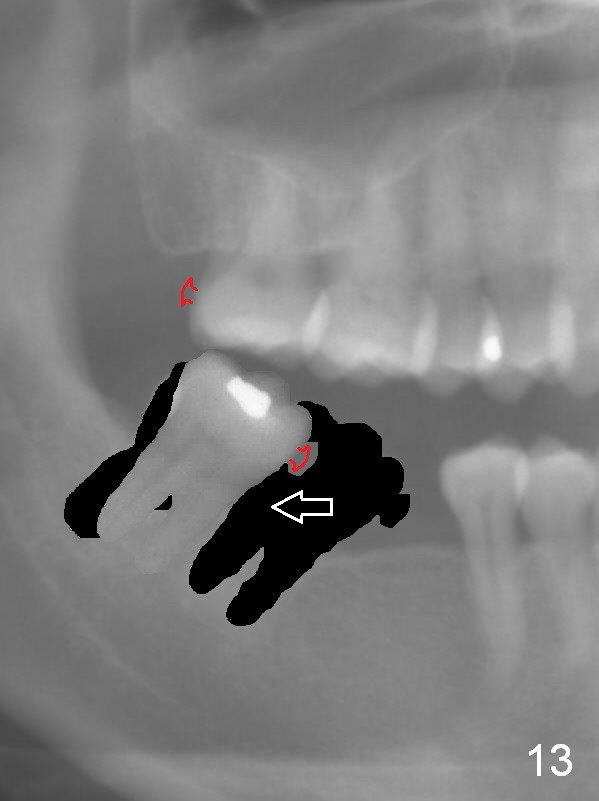

Four weeks of using open coil spring between #29 and 31, these teeth seem to have rotated (Fig.8,9 curved arrows). After placing a longer spring and the same arch wire, power chains are installed to close the anterior diastema (Fig.10 ^). The patient notes the divergence between #20 and 21 (Fig.11). To correct the latter, either place #20 bracket more distal (Fig.11 *) or place power chains between these teeth only. To facilitate #31 distalization (Fig.13), place lingual buttons (Fig.12 red) in the mesial surface of #31 and the distal of #2 with an elastic between the buttons.